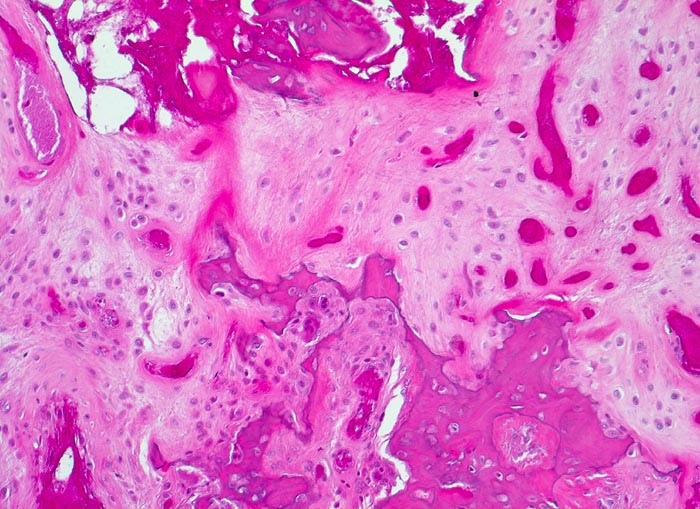

• Flächenhafte Ablösung des gut erhaltenen Gelenkknorpels zwischen subchondraler Knochenlamelle und angrenzender nekrotischer Spongiosa.

• In der Nekrosezone osteoklastäre Resorption von avitalen sequestrierten Spongiosabälkchen.

• Ortsständiger Lamellenknochen wird als Leitschiene zur Fasernknochenneubildung benutzt.

• Pseudozystische Hohlräume in den nekrotischen Markräumen.